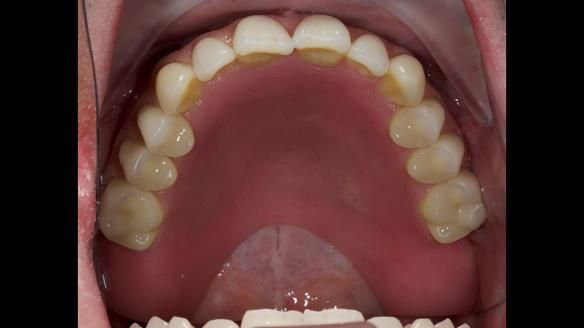

Welcome to my Newsletter 57, where I show the making and fitting of complete dentures supported by upper and lower dental implants for Alisdair. This issue provides a comprehensive overview of the entire protocol workflow.

3. Both upper and lower dentures can be enhanced in appearance.

The detailed clinical situation and treatment process are outlined below, with clinical work provided by me and technical work by Rowan Garstang. New complete implant supported complete dentures were made. The new upper denture had ‘almost’ full palatal extension for the non-splinted implants following ITI guidelines. A decision was reached to retain the worn Kerator attachments, as their removal could potentially accelerate implant failure. The treatment spanned five visits for denture fitting and one review. Alisdair expressed great satisfaction with the treatment, noting a significant enhancement in his overall quality of life.